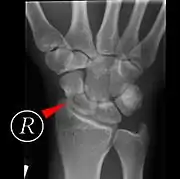

Scaphoid fracture before and after operation

Fractures of the scaphoid are the most common of the carpal bone injuries, because of its connections with the two rows of carpal bones.[1]:177

The scaphoid can be slow to heal because of the limited circulation to the bone. Fractures of the scaphoid must be recognized and treated quickly, as prompt treatment by immobilization or surgical fixation increases the likelihood of the bone healing in anatomic alignment, thus avoiding mal-union or non-union.[5] Delays may compromise healing. Failure of the fracture to heal ("non-union") will lead to post-traumatic osteoarthritis of the carpus.[1]:189 One reason for this is because of the "tenuous" blood supply to the proximal segment.[2] Even rapidly immobilized fractures may require surgical treatment, including use of a headless compression screw such as the Herbert screw to bind the two halves together.

Healing of the fracture with a non-anatomic deformity (frequently, a volar flexed "humpback") can also lead to post-traumatic arthritis. Non-unions can result in loss of blood supply to the proximal pole, which can result in avascular necrosis of the proximal segment.

Scaphoid fractures may be difficult to diagnose via plain x-ray. A repeat x-ray may be required at a later date, as might cross-sectional imaging via MRI or CT scan.[5]